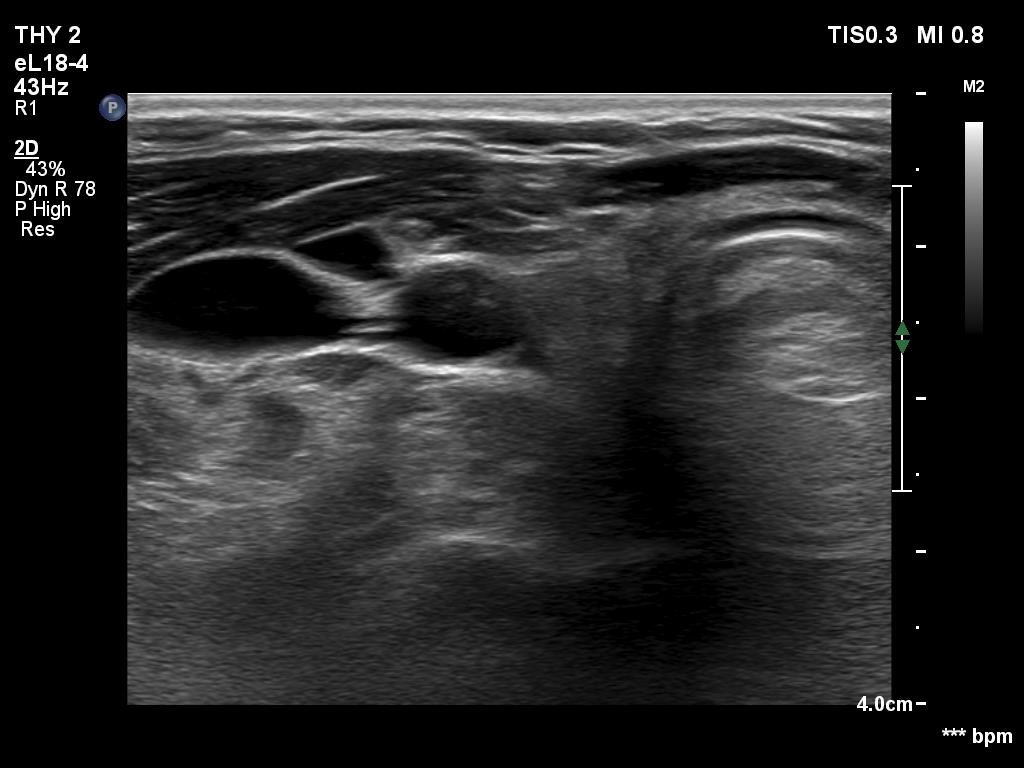

Ultrasonography. The right lobe was replaced with connective tissue. A hypoechoic mass was found in the left thyroid bed. On certain sections, this mass was very similar to a muscle fiber, however some other sections proved the presence of intralesional echogenic figures; the presence of back wall cystic figures was obvious but in the event of some granules microcalcifications should be considered. The lesion was vascularized, which excluded that the mass is muscle fiber.